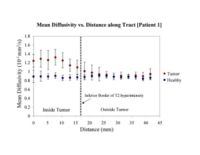

Clustered fibers in the region of the corticospinal tract have been used to identify regions of interest for slice-by-slice measurements of its diffusion properties in normals and tumor subjects. A pilot study (with Monica Lemmond at Harvard Medical School and Stephen Whalen and Alexandra Golby at Brigham and Women's Hospital/HMS) has demonstrated changes in tumor-affected tracts (relative to the contralateral side) beyond the apparent tumor border. A larger study is currently underway.

Monica E. Lemmond, Lauren J. O'Donnell, Stephen Whalen, and Alexandra J. Golby Characterizing Diffusion Along White Matter Tracts Affected by Primary Brain Tumors Abstract accepted to HBM 2007